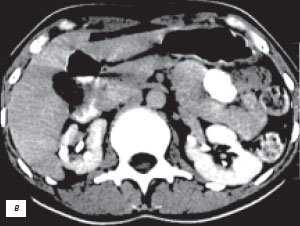

(Справа) КТ, аксиальная проекция, кортико-медуллярная фаза контрастирования: дорсальная половина межполюсной области почки, контрастируемая аналогично корковому веществу почки. На последующих фазах выявлено гомогенное контрастирование почки.

(Справа) КТ с контрастированием, аксиальная проекция: у этого же пациента установлено, что «объемное образование» — это нормальное корковое вещество почки, которое инвагинирует в почечную лоханку между чашечками верхнего полюса и меж полюсной областью почки. Обратите внимание на нормальный внешний контур почки. Бертиниевы колонны чаще всего выявляют с одной стороны и слева, как в данном случае: в 18% случаев они могут быть двусторонними.